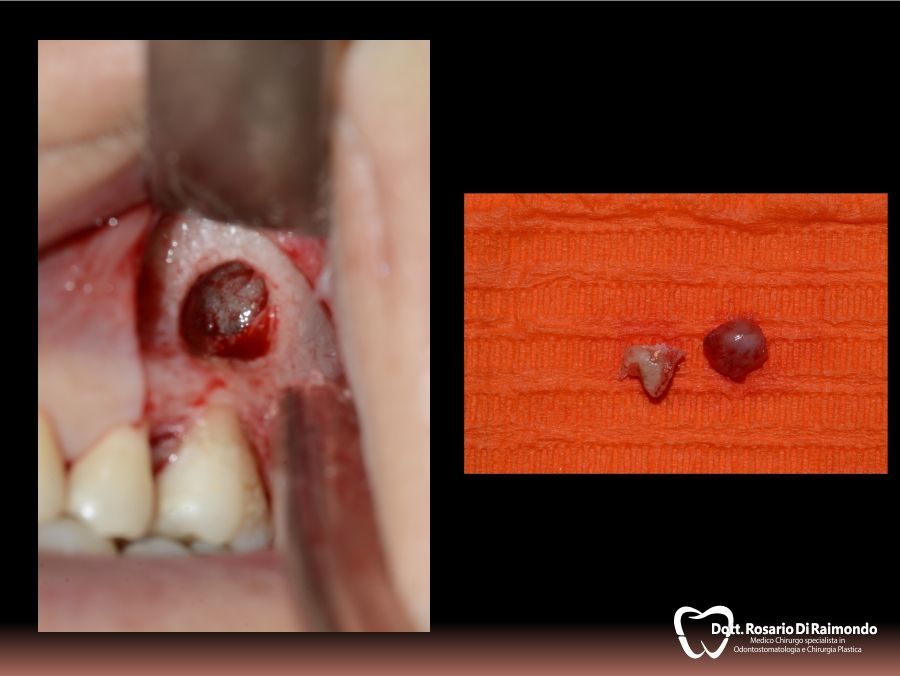

Cisti

La cisti è una formazione patologica che presenta una forma generalmente sferica ed ha la tendenza ad un lento accrescimento asintomatico a spese dei tessuti circostanti.

L'aumento di volume di una cisti può portare al riassorbimento delle radici di denti contigui e dei tessuti ossei che la contengono. In altre occasioni si può verificare la dislocazione degli elementi dentali adiacenti.

La posizione e la velocità di crescita di una cisti sono due dei fattori che il dentista prende in considerazione nel decidere se procedere alla rimozione chirurgica della stessa o monitorarla nel tempo tramite controlli clinici e radiografici periodici.

Granulomi

Il granuloma dentale (detto anche granuloma apicale), è una neoformazione infiammatoria cronica a livello dell’apice dei denti di origine batterica e nella maggior parte dei casi è asintomatico, anche se tuttavia può causare la presenza di fistole nella gengiva con fuoriuscita di pus. I granulomi apicali si diagnosticano mediante Rx endorale e il suo trattamento consiste nella terapia canalare (endodonzia del dente o ritrattamento endodontico) e terapia antibiotica.

Apicectomie

L'apicectomia è un piccolo intervento chirurgico rivolto a rimuovere il granuloma apicale nei denti malati in cui la terapia canalare tradizionale non prospetta un risultato predicibile.

In molti casi, la rimozione del granuloma dentale si associa alla asportazione dell'apice radicolare.

L'indicazione più frequente per l'apicectomia è l'insuccesso di una terapia endodontica di un elemento dentario la cui conservazione è ritenuta necessaria.

Casi Trattati

Di seguito riportiamo alcune fotografie di casi esplicativi di Chirurgia Orale.